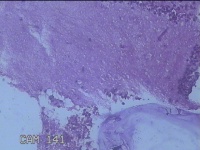

宫颈赘生物

性别

女

年龄

29岁

临床诊断

早期人工流产;宫颈赘生物

一般病史

人流见宫颈口有1赘生物。

标本名称

大体所见

灰白暗红色肿物1.3x0.8x0.3cm一个,表面糜烂。

图2